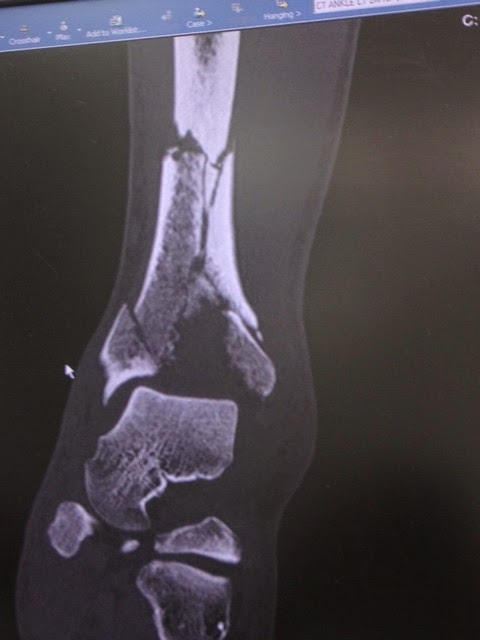

On February 10, 2013, I took an awkward fall while skiing and heard the crunch of multiple bones breaking in my leg. When I was taken to first-aid at the mountain and they removed my ski boot, the orthopedist on-site said he wasn't even going to bother taking an x-ray as it was clear that from how my foot was hanging and the multiple bones pushing against the skin that I would need surgery.

The next morning I was in Dr. Levine's office and the x-ray and MRI confirmed that I had indeed shattered my tibia into multiple pieces (x-ray and MRI attached). Surgery was scheduled for 3 days later on Valentine's Day 2013. The surgery lasted just shy of 6 hours as Dr. Levine pieced my leg together with multiple plates and a more than a dozen screws (post-surgery x-ray attached). The anesthesiologists (Drs. Michael Gordon, James Beckman, and Seth Waldman), Dr. Levine's PA, Lisa Pearson, and the entire staff were fabulous.